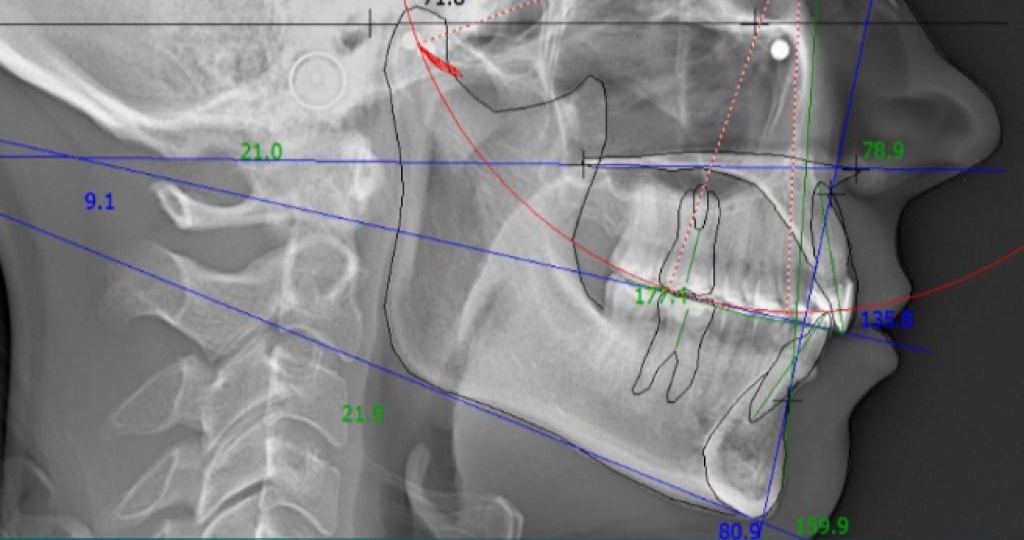

А ваш ортодонт делает расчет ТРГ?

Разбирая клинические случаи, мы часто показываем вам изображения телерентгенографии пациентов. Что же это такое? Телерентгенография (далее ТРГ) — это рентгенологическое исследование, которое представляет собой 2D-снимок в боковой или прямой проекции черепа человека. ☝🏼 По данному снимку компетентный врач диагностирует аномалии, которые имеются у конкретного пациента в различных плоскостях. С помощью снимков ТРГ можно просчитать довольно много параметров и диагностировать особенности строения зубочелюстной системы. 🔸 Размеры и положение челюстей (прогнатия, ретрогнатия). 🔸 Макро- и микрогнатия (увеличенная или недоразвитая нижняя челюсть). 🔸 Взаимоотношение челюстей. 🔸 Инклинация резцов. 🔸 Направление окклюзионной линии. 🔸 Взаимоотношение мягких тканей лица и челюстных костей. Также на ТРГ могут быть измерены углы и расстояния, которые характеризуют соотношение различных элементов зубочелюстной системы. 👨🏻⚕️ ТРГ является одним из исследований в практике врача-ортодонта и врача